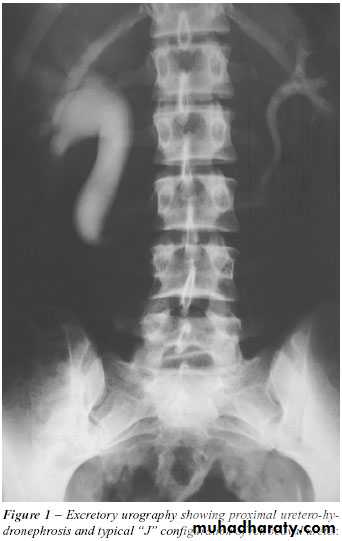

18- PUJ obstruction

20- PUJ obstruction

22- PUJ obstruction23- horse shoe24- PUJ obstruction25- double ureter26- partial PUJ obstruction27- double ureter28- schistosoma of bladder29- filling defect in the pelvi-calycial system30- tumor 31- filling defect (stone)

33- PUJ obstruction